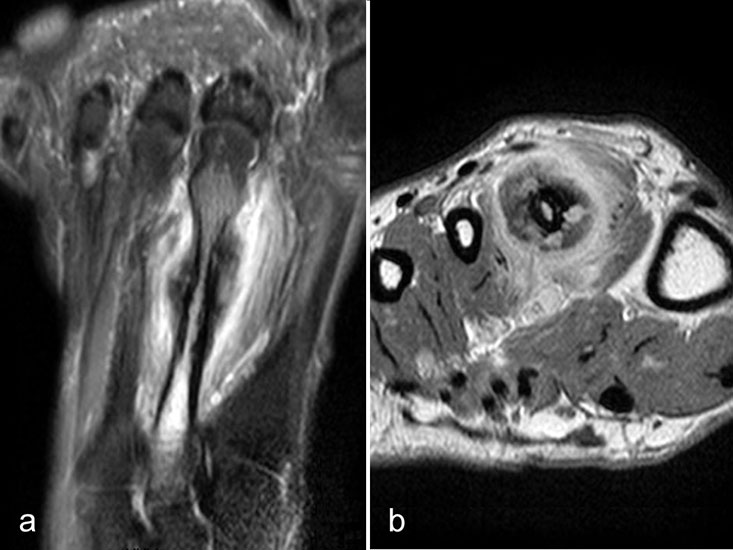

Intermetatarsale Bursitis

Intermetatarsale Bursitis bei rheumatoider Arthritis mit Erguss (a) und deutlicher Synovialitis in mehreren Schleimbeuteln (b).

Zwischen den Metatarsaleköpfchen befinden sich kleine Schleimbeutel, die in der Regel MR-tomographisch nicht zu identifizieren sind. Sie werden erkennbar, wenn sie zarte Flüssigkeitsstreifen enthalten, was noch nicht als pathologisch zu werten ist. Eine signifikante Distension und vor allem eine verstärkte Kontrastmittelanreicherung sind Ausdruck einer Bursitis. Die isolierte Bursitis intermetatarsal ist selten und stets hochverdächtig für das Vorliegen einer rheumatischen Grunderkrankung (Abb. 13).

Häufig sind intermetatarsale Bursitiden als Begleitphänomen bei Rupturen oder Degenerationen der plantaren Platte und auch bei Morton-„Neuromen“.